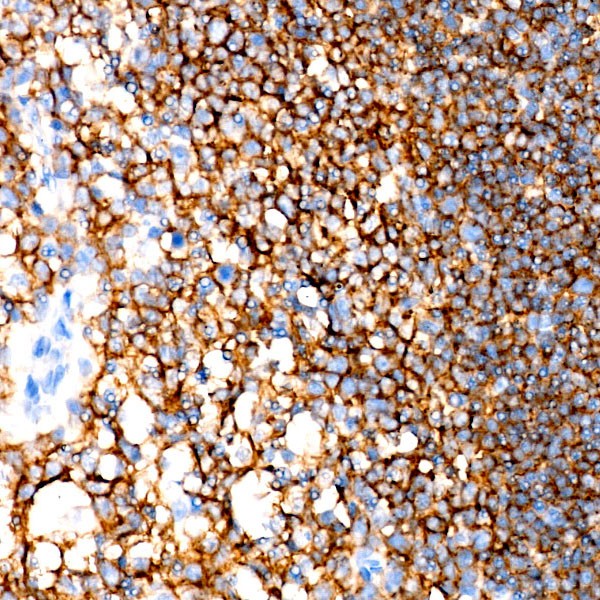

Images of CD19 Rabbit mAb (A23278)

Immunohistochemistry analysis of CD19 in paraffin-embedded human tonsil using CD19 Rabbit mAb (A23278) at dilution of 1:300 (40x lens).Perform high pressure antigen retrieval with 10 mM Tris/EDTA buffer pH 9.0 before commencing with IHC staining protocol.